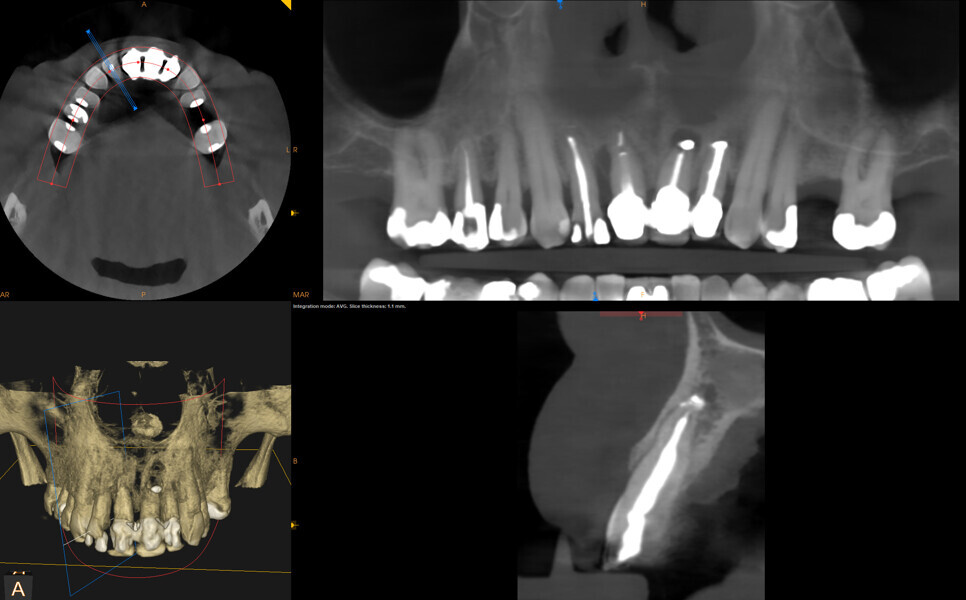

The first step was to obtain a CBCT scan of the maxillary arch, which revealed periapical pathology in teeth #12-22 (Figs. 2 & 3). Furthermore, tooth #21 exhibited significant loss of buccal bone, and a small piece of amalgam was identified in the bone near tooth #21. After a thorough analysis of the radiographic findings, a treatment plan was established to extract teeth #12-22 and perform ridge preservation to reduce bone loss in the extraction sites.

Fig. 2: Initial CBCT scan of the maxillary arch.

Fig. 3: Initial CBCT scan. Coronal view of tooth #21 showing buccal bone loss.